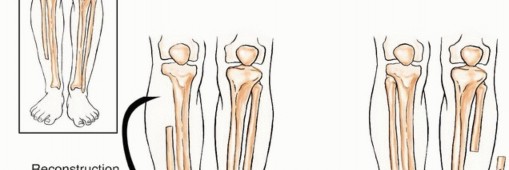

الجراحة هي حجر الزاوية في علاج معظم أورام الشظية، سواء كانت حميدة عدوانية أو خبيثة. يبرع الأستاذ الدكتور محمد هطيف في تقنيات الحفاظ على الطرف، والتي تهدف إلى إزالة الورم بالكامل مع الحفاظ على أكبر قدر ممكن من العظم والأنسجة السليمة المحيطة لضمان أفضل وظيفة ممكنة بعد الجراحة.

أ. أنواع الاستئصال الجراحي

تُصنف جراحات استئصال الأورام العظمية بناءً على مدى الإزالة: